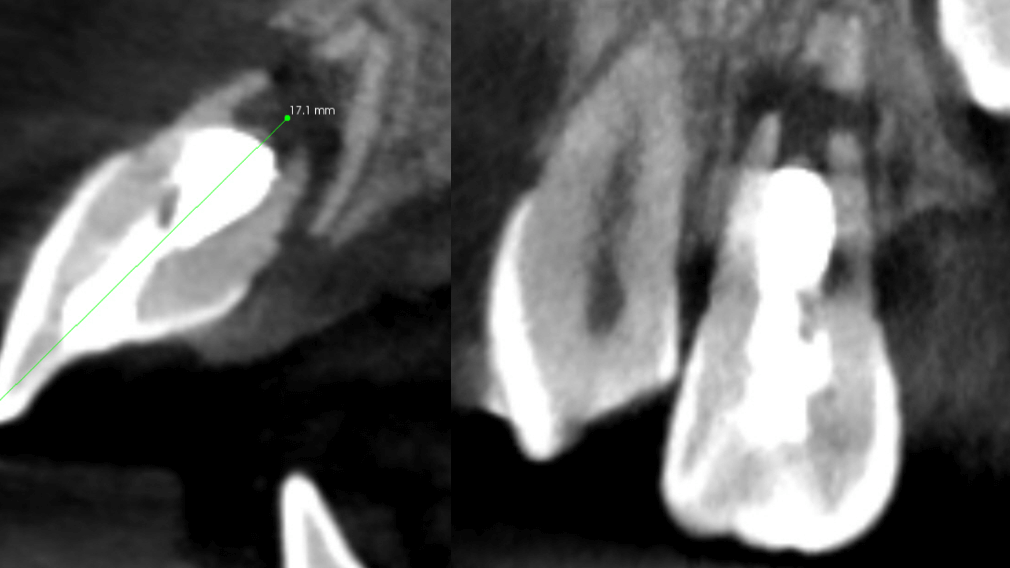

CBCT showing apical bone destruction and fracture of cortical plates.